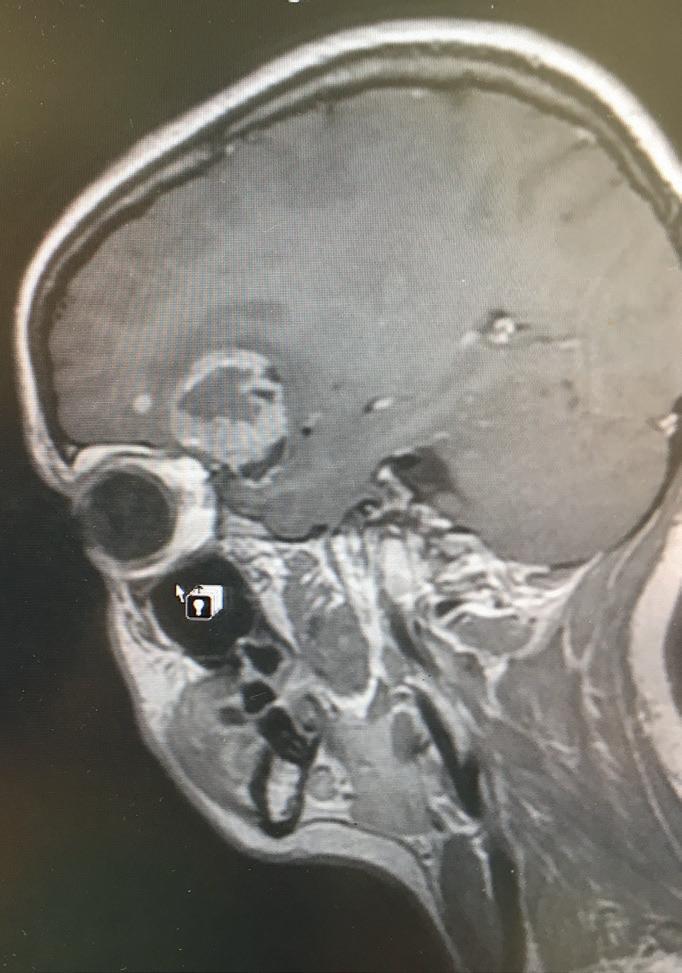

Apoignant anniversary approaches –22nd May marks two years since the world lost Laura Nuttall, a vibrant 23-year-old taken too soon by a glioblastoma (GBM). Glioblastoma multiforme is a fast-growing type of tumour of the brain. It is the most common type of primary malignant brain tumour in adults. Horrified by the statistics around brain tumours and the lack of government investment, Laura’s mum, Nicola Nuttall, became a dedicated campaigner and is continuing her eldest daughter’s passion to raise awareness and find a cure.

Eight tumours. Glioblastoma multiforme. The most aggressive form of brain cancer. For any family, this news would be shattering. “It was a complete shock,” Nicola recalls. “Laura was in her first term at university in London. We had to pack up her room and bring her home to Barrowford. Then the search began – finding a surgeon, registering with a local GP. The immediate priority was surgery to remove the largest tumour, the one causing her headaches, nausea and seizures.”

The standard treatment in the UK involves surgery followed by radiotherapy and chemotherapy. Laura bravely underwent this gruelling regime. “But even with all that,” Nicola explains, “her prognosis was just 12 months. We refused to accept that. We started researching treatments available elsewhere. In Germany, we found a professor using electro hyperthermia and oncolytic virus therapy. It made sense to us, so we started fundraising to take her to Cologne every six weeks for these treatments. Without the incredible generosity of our community, that wouldn’t have been possible.”

campaigning for whole genome sequencing of brain tumours. “Brain tumours are incredibly heterogeneous,” she explains. “Each one has its own genetic fingerprint. Yet, we still treat them all with the same chemotherapy, even though there could be more effective, targeted treatments. Brain tumours are the biggest cancer killer of children and adults under 40, yet they receive only about 2 per cent of cancer research funding. There have been no new drugs for the disease in decades. We need personalised treatments, targeted to the specific drivers of each tumour and we need faster diagnosis.”

March marks Brain Tumour Awareness Month in the UK, a crucial time to raise awareness of this often overlooked and devastating disease

Brain tumours can develop at any age, from young children to older adults. They are complex and varied, with over 120 different types, each presenting unique challenges in diagnosis and treatment. Glioblastoma (GBM), the most aggressive form, is particularly devastating, often diagnosed late and notoriously difficult to treat. The insidious nature of brain tumours, often mimicking other ailments, can lead to delayed diagnosis, impacting prognosis and treatment options.